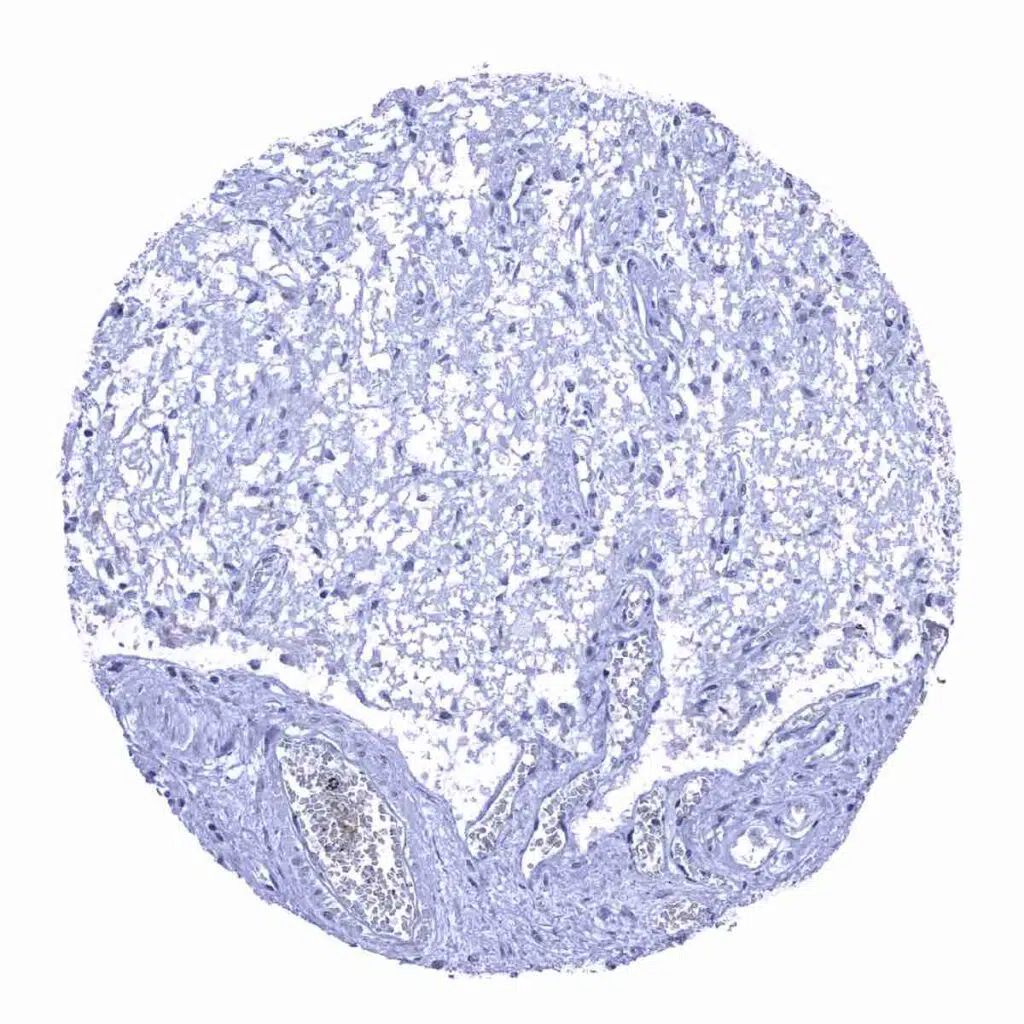

Lymph node – A fraction of plasma cells are Rabbit anti-human IgA positive.